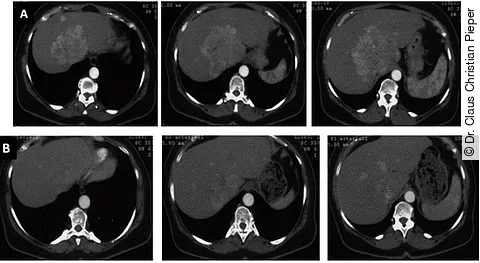

Patient mit großem, zentral gelegenem HCC mit mehreren Satellitenherden unmittelbar vor (oben) und 24 Monaten nach der Radioembolisation (unten).

Bei Patienten mit nicht operablem Leberzellkarzinom (HCC) steht mit der Radioembolisation eine Therapie zur Verfügung, die auch im fortgeschrittenen Stadium sicher und effektiv ist. Im Vergleich zu anderen Therapien wird die Behandlung von den Patienten gut vertragen.